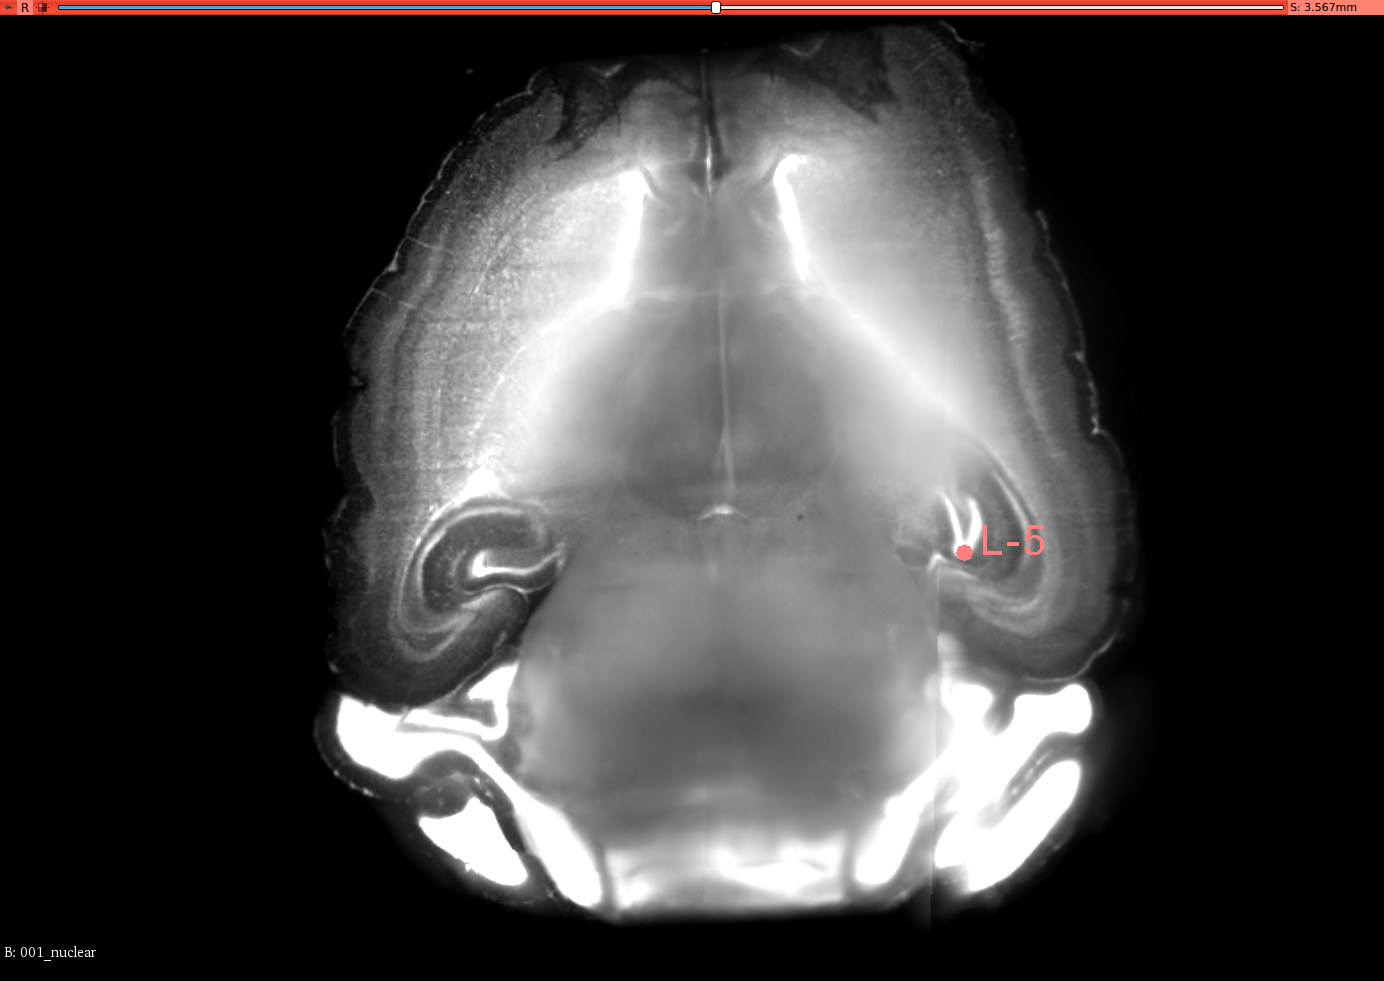

To validate the registration performance of the proposed methods and comparing the baseline methods in a more objective manner, a landmark registration test is conducted. In the CUBIC dataset, three brains are used to test the registration performance. In the landmark test, the same dataset is used for the performance validation. 12 landmarks are selected and all of these landmarks are selected where their positions vary in all three axis. 3D slicer tool is used to select the landmarks for this experiment from the CUBIC brains. A set of selected landmarks are shown in Figure 7. Table 3 shows the results of the 3D landmark registration by proposed InvGAN method and other baseline methods. The Euclidean distance between the registered landmarks and reference landmarks are presented in mm. For optimisation-based ANTS and Elastix tools, the same parameter sets are used to register landmarks selected from moving image and fixed image. After the registration, the output point locations are compared with reference point locations in the fixed image. For the deep-learning-based VoxelMorph and InvGAN, the deformation values in X,Y and Z are extracted from the same voxel location of the selected landmark’s voxel location. After applying deformation to the landmarks, the new position is compared with that of corresponding reference points in the fixed image.

Refer to caption

(a) Brain-1

(b) Segittal View

(c) Coronal View

(d) Corresponding Points in Brain003

(e) Segittal View

(f) Coronal View

(g) Brain-2

(h) Segittal View

(i) Coronal View

(j) Corresponding Points in Brain-3

(k) Segittal View

(l) Coronal View

Figure 7: 3D Landmarks